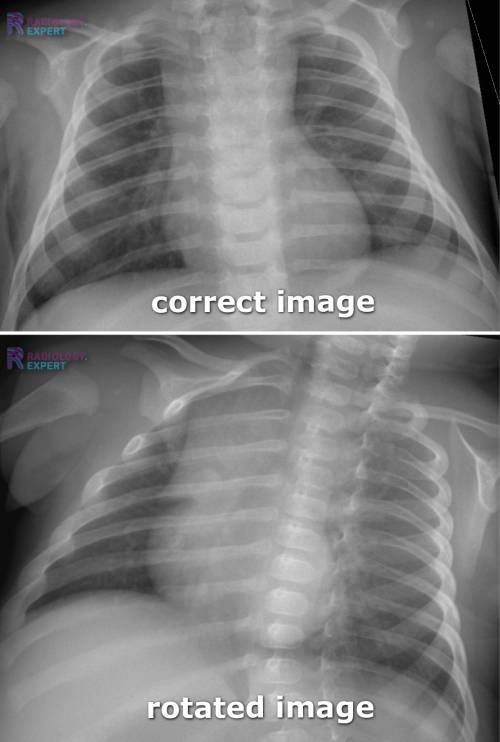

How To Tell If X Ray Is Rotated . This patient is rotated to their left (right shoulder forwards and left shoulder backwards) the spinous processes are not midway between the medial ends of the clavicles. rotation is expressed by describing patient obliquity in relation to the film or cr device. Trachea, carina, bronchi and hilar. If the patient is rotated to their right, then heart size may be underestimated. On ct however there is a cyst connected to. In a radiograph in which the patient is rotated right. If the patient is rotated to their left, then the heart may appear enlarged. This can make structures (like the heart) appear. A small amount of patient rotation can lead to misinterpretation. This results in exaggeration of heart size.

Chest Xray child How To Tell If X Ray Is Rotated This results in exaggeration of heart size. If the patient is rotated to their right, then heart size may be underestimated. A small amount of patient rotation can lead to misinterpretation. If the patient is rotated to their left, then the heart may appear enlarged. On ct however there is a cyst connected to. In a radiograph in which the. How To Tell If X Ray Is Rotated.